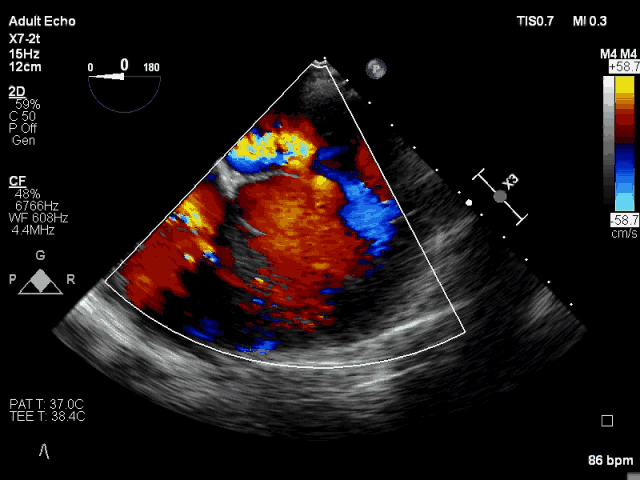

术前TEE CDFI示MR重度